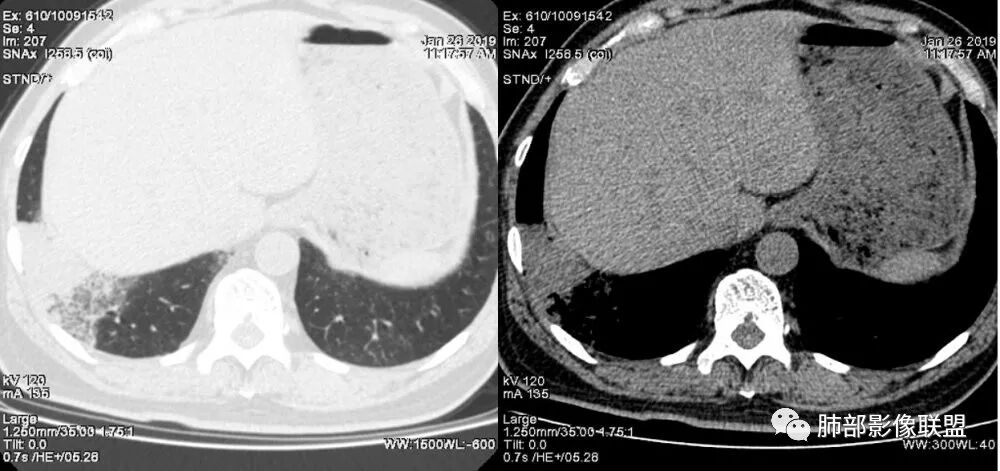

肺炎性肺癌,是一种影像学上表现为实变、斑片或大片状模糊阴影的肺癌。肺炎性肺癌影像表现不典型,是周围型肺癌的一种,病理类型多见于肺腺癌,少许见于鳞癌、小细胞肺癌,而肺腺癌中以粘液腺癌多见。

粘液腺癌是一种原发性肺腺癌的变异型,病理上起源细支气管壁以远的支气管与肺泡上皮,属于周围型;其细胞形态及排列方式与非粘液性腺癌有所不同,为成簇排列的粘液腺上皮,很早就有细胞内粘液及分泌细胞外粘液;早期粘液腺癌常为一单发结节,有沿气道距离播散的能力,中后期肿瘤细胞随粘液飘向更远的肺段及肺叶,会出现斑片状肌片状实变和/或磨玻璃密度样的肺炎样影像学改变;随着肺粘液腺癌体量的增大,粘液的播散,临床上会有咳白痰,查痰液脱落细胞会找到肿瘤细胞。

1.本例病灶较大片混杂密度影,胸膜下分布为主(未沿着支气管分布),该分布特点可见于大叶性肺炎、干酪性肺炎、淋巴瘤及粘液腺癌等。可惜未提供增强扫描图像。

2.病灶示中央实变区,周围GGO,可见明显小叶间隔增厚,GGO边界清楚,应当考虑到恶性病变的可能性。肺炎因炎性水肿及渗出,影像上边界常模糊不清,注意早期粘液腺癌可出现似清非清的边界。粘液腺癌因粘液成份较多,密度一般偏低,纵隔窗病灶常会消隐或范围会明显缩小,这不同于炎性实变。

3.病灶内支气管走形略显僵直,侧支少(粘液阻塞),也符合肺腺癌的枯树枝征。而大叶性肺炎的支气管是管壁光整、通畅、自然,结核的支气管常常壁增厚,甚至狭窄后扩张;

4.患者临床症状不重,临床炎性指标不高,结合肺内影像,应警惕肺炎型肺癌。

如果患者临床症状不重,与影像表现不适格,咳大量白痰,炎性指标不高,抗感染治疗肺部病灶未见吸收,或反见扩大及其他肺组织内出现飘散的磨玻璃结节,因高度怀疑粘液性肺癌!